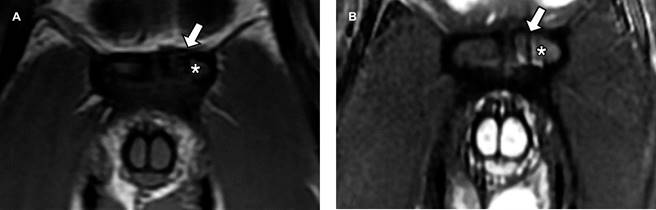

Se realizó ultrasonido inguinal y radiografía anteroposterior de pelvis las cuales no mostraron alteraciones; posteriormente, se decidió realizar resonancia magnética de pubis: en plano coronal (Figura 1) se observó fractura vertical en el cuerpo del hueso púbico izquierdo (flecha blanca en A y B) con edema de tejidos blandos adyacente (asterisco en A y B); en plano axial (Figura 2) se identificó fractura en la porción anterior del cuerpo del hueso púbico izquierdo (flecha blanca en A y B), existe osteítis púbica bilateral de predominio izquierdo (asterisco en A y B) y en plano sagital (Figura 3) se observó edema óseo a nivel de la placa aponeurótica del recto abdominal y aductor largo bilateral (flecha amarilla en A y B) de predominio izquierdo; además de desgarro en la placa aponeurótica izquierda (flecha verde).

Figura 1: Resonancia magnética de pubis. A) T1 plano coronal. B) STIR plano coronal. Se observa fractura de trazo vertical en el cuerpo del hueso púbico izquierdo (flechas blancas en A y B) con edema óseo adyacente (* en A y B).